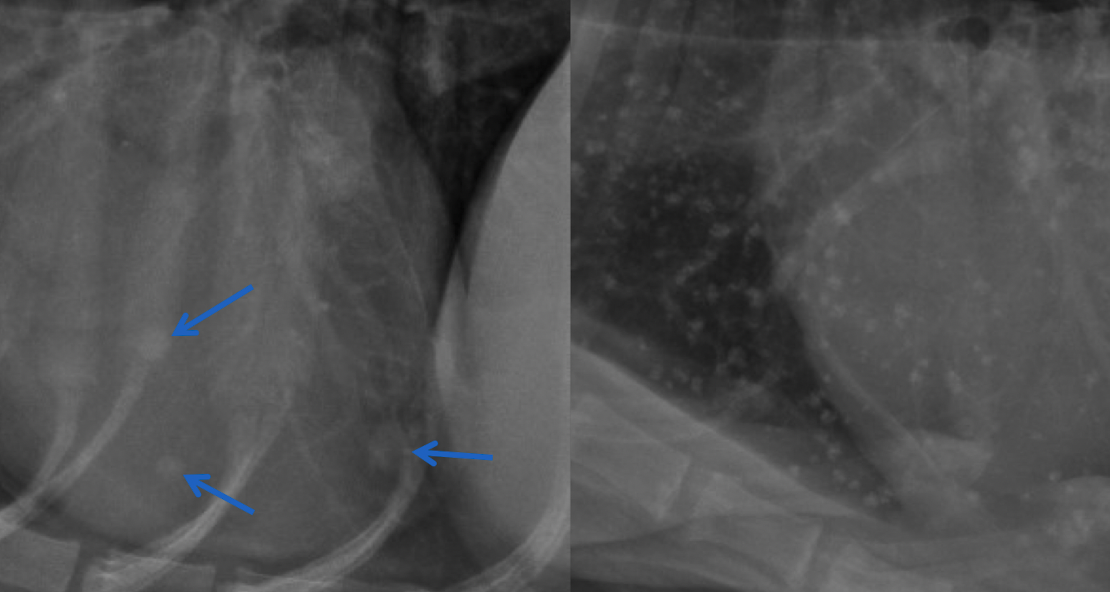

what kind of pattern

normal- left

interstitial- right